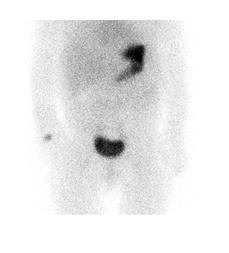

Figure 7 : Adolescente admise avec hémorragie basse massive. Préparation avec famotidine intraveineuse. Mise en évidence sur l’étude dynamique ( A ) puis sur le cliché statique ( B ) d’un foyer ombilical augmentant en intensité et en taille (flèche). La relation du diverticule contenant de la muqueuse gastrique avec l’ombilic est bien démontrée sur le SPECT-TDM (C). La pathologie de la chirurgie effectuée dans la foulée via laparotomie et non laparoscopie étant donné les trouvailles a démontré un Meckel de 6 x 2 cm contenant de la muqueuse gastrique, avec aspect perforé associé à un canal omphalomésentérique de 0,5 x 0,5 x 0,5 cm. Moins de 4 heures se sont écoulées entre l’arrivée de la patiente à l’urgence et la chirurgie.

Figure 9 : Patiente de 8 mois avec épisodes de méléna et un épisode de rectorragie amenant une consultation à l’urgence. Deux foyers de captation dont un est rénal, mieux identifié sur le cliché latéral (flèche mince), qui diminue au cours du temps et le second est suspect malgré sa localisation paramédiane gauche (flèche épaisse), qui augmente en parallèle avec l’ estomac. Opérée le jour même avec résection d’un Meckel proche de l’ombilic. Étude dynamique ( A ) et statiques (B) en incidences antérieure et latérale gauche, et images de fusion SPECT-TDM (C).